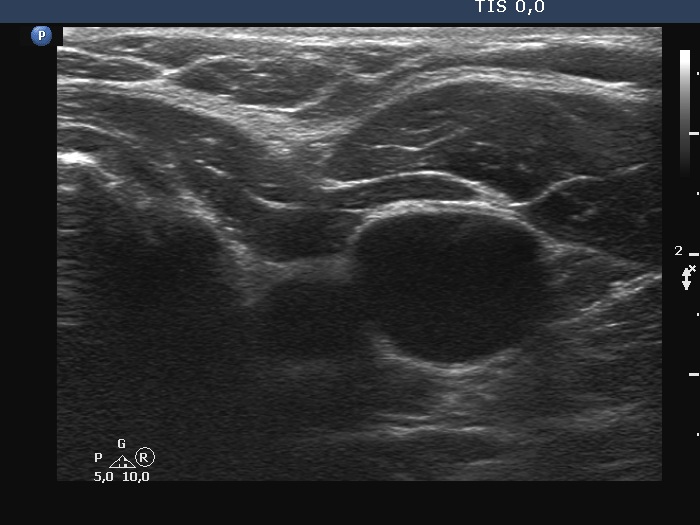

Follow-up investigation a year after the surgery (ultrasonographic picture 3)

Right lobe, longitudinal scan

Left lobe, transverse scan. The deeply hypoechoic mass is a vessel.